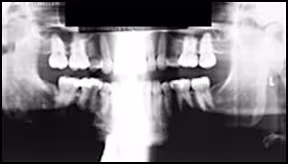

Figure 26. Optimal Panoramic Image.

Example of an excellent edentulous panoramic radiographic image with adequate exposure and correct anatomic representation.